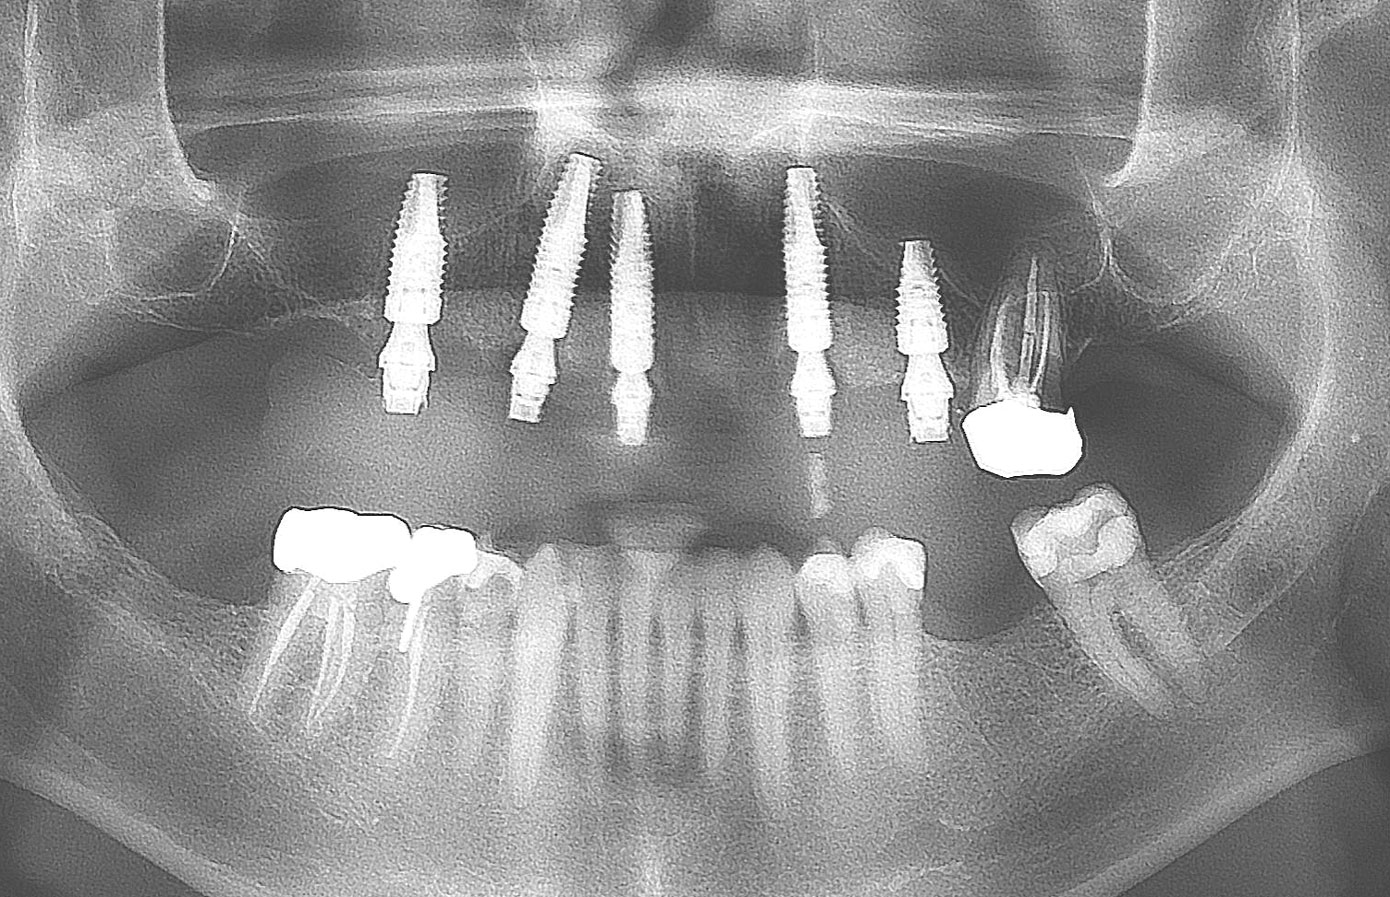

Fig 40. Postoperative panoramic radiograph on the day of surgery.

Figure 40

Fig 41. Postoperative periapical x-rays on the day of surgery demonstrating ideal immediate implant placement in bone.

Figure 41

Fig 42. Postoperative periapical x-rays on the day of surgery demonstrating ideal immediate implant placement in bone.

Figure 42